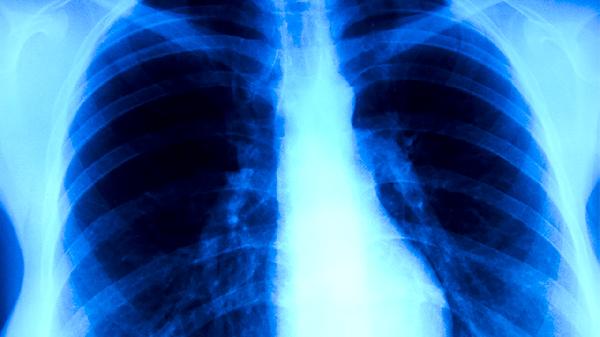

胸部X線或CT檢查能發(fā)現(xiàn)肺結(jié)核特征性病變,如肺上葉尖后段浸潤影、空洞形成等。影像學(xué)表現(xiàn)需與肺炎、肺癌等疾病鑒別,活動性病變多呈現(xiàn)邊緣模糊的斑片狀陰影。該方法無法區(qū)分活動性與陳舊性病灶,需結(jié)合臨床癥狀和其他檢測綜合判斷。兒童肺結(jié)核患者可能僅表現(xiàn)為肺門淋巴結(jié)腫大。